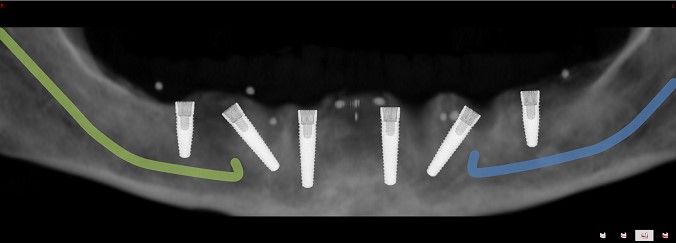

Bei der All-on-6 bzw. der All-on-8 Versorgung handelt es sich um eine komplexe Implantation, die nur von erfahrenen Zahnärzten und Implantologen angewandt wird. Um den eigentlichen chirurgischen Eingriff durchzuführen, sind diverse Vorbereitungen und Planungsarbeiten notwendig. Dazu zählen dreidimensionale Röntgenaufnahmen mit digitaler Volumentomografie (DVT) von Schädel und Kiefer, Berechnung von Bohrwinkeln und Bohrtiefe, Anfertigung von Bohrschablonen und das sogenannte Backward-Planning. Dies bedeutet eine computergestützte Vorgehensweise, um das passende Langzeitprovisorium vorab herzustellen und die Ergebnisse bereits vor der Operation zu visualisieren. Hierbei arbeiten Behandler und Zahntechniker eng zusammen. Die genannten Maßnahmen helfen, nicht nur Ästhetik und Funktionalität deutlich zu erhöhen, sondern das Einsetzen der künstlichen Zahnwurzeln wird sicherer und schonender, da Nervenverläufe und anatomische Besonderheiten genau bekannt sind und berücksichtigt werden.

Bildquelle: ©GZFA Versorgung des Unterkiefers mit einer Keramikbrücke auf 6 Implantaten.

Das All-on-6 Behandlungskonzept: Zahnbrücke aus Vollkeramik auf 6 Implantaten für den Unterkiefer

Bei kompletter Zahnlosigkeit des Unterkiefers benötigt man beim All-on-6 Behandlungskonzept 6 Implantate, um festen Zahnersatz aus Zirkonoxidkeramik zu fixieren. Für herausnehmbaren Zahnersatz genügen normalerweise 4 künstliche Zahnwurzeln.